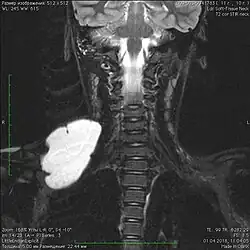

Пороки развития лимфатических сосудов в области головы и шеи чаще всего определяются при рождении или в первые годы жизни ребёнка, в возрасте до одного года в 60-80 % случаев[6]. Основными методами визуализации лимфатической мальформации являются ультразвуковое исследование (УЗИ) и магнитно-резонансная томография (МРТ). Данные исследования позволяют определить площадь и объём патологических тканей, размеры кист, топографию образования.

В настоящее время лимфатическую мальформацию можно визуализировать у плода с конца первого — начала второго триместра беременности. Лучше всего определяются крупно кистозные формы мальформаций. Чаще всего лимфатические мальформации выявляются в области шеи, грудной клетки, языка, туловища и конечностей.[14][15]